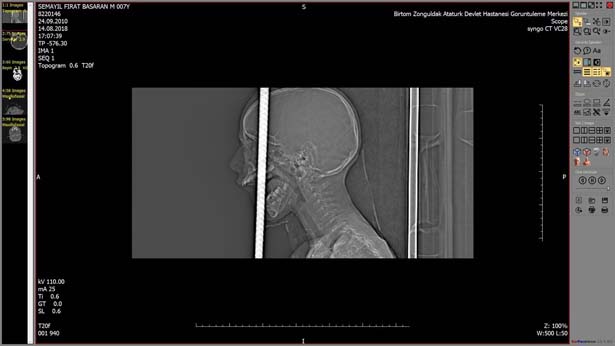

Zonguldak'ta, bisikletiyle gezerken 2 metre yükseklikten düşen 7 yaşındaki Fırat Başaran'ın ağzından giren demir başından çıktı. Yaralı çocuk, ekipler tarafından Bülent Ecevit Üniversitesi Uygulama ve Araştırma Merkezine sevk edildi. Beyin cerrahisi, kulak burun boğaz, plastik cerrahisi, anestezi ve AFAD ekipleri başarılı bir ekip çalışması sonucunda 6 saat süren operasyonla 1 metre uzunluğundaki demir çubuk operasyonla alındı. Çocuk yoğun bakım ünitesine kaldırılan 7 yaşındaki Fırat Başaran'ın tedavisi devam ediyor.

İlk günlerin büyük önem taşıdığını ifade eden Beyin ve Sinir Cerrahisi Anabilim Dalı uzmanı Doç.Dr. Şanser Gül ise, "Hastamızı ilk olarak Atatürk Devlet Hastanesinde beyin cerrahisi uzmanı operatör Dr. Emrah Keskin görüyor ve durumu bize haber veriyor. Biz hazırlığımızı yaptık. Temel prensip ilk önce zarar vermeme, üst damaktan ağız içinden giren ve yaklaşık 1 metre uzunluğundaki demir çubuk kafatasını delerek sol ön fontelden 40 santim dışarı çıkmıştı. AFAD ekipleri tarafından 3 santim kalana kadar kesildi. Temel prensiplere bağlı kalarak parçalanan bölgeyi genişleterek demir çubuk rahatlatıldı. Sonra ameliyata alınarak demir çubuk çıkartıldı. Ön beyin düşünce davranışlarımızı yönlendirir; hafıza, düşünme, karar verme, idare etme gibi durumları evet çocuğumuz şu an yoğun bakımda bilinci açık bir şekilde zaman içinde neyi kaybettiğini görmüş olacağız. İlk günlerde hayati önem taşıyan bir durum var o da enfeksiyon ekip olarak tüm işlemler yapıldı. Antibiyotik tedavisine başlandı. İlerleyen günler her türlü sonuca açık" şeklinde konuştu.